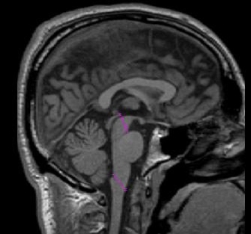

The three parts of the brainstem include the midbrain (mesencephelon), the

pons, and the medulla. The most superior part of the brainstem is the midbrain

which continues behind the pons and down to the medulla. The more anterior,

superior part of the brainstem is the pons and the more posterior, inferior

part of the brainstem is the medulla, although there is some overlap. The

pons is an apple shaped structure, which sits on the anterior side of the

more stalk-like medulla. The medulla leads directly into the spinal cord.

The posterior border of the brainstem is the cerebellum, although cerebellum

and brainstem are present at the same time. The brainstem is bordered superiorly

by the diencephalon and inferiorly by the spinal cord. The superior colliculi

and inferior colliculi (seen as two bumps on top of the brainstem in more

posterior slices) are included as brainstem.

Draw two sulci lines in the sagittal view to determine the superior/inferior

borders of the brainstem.

1. For the first sulci line, draw the superior brainstem line as a straight

diagonal line extending from the tip of the posterior commissure to the prepontine

fissure to mark the border between the pons and the midbrain. In coronal sections

this line will mark the superior border of the brainstem from the ventral diencephelon

(VDC).